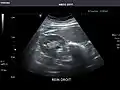

Left kidney -